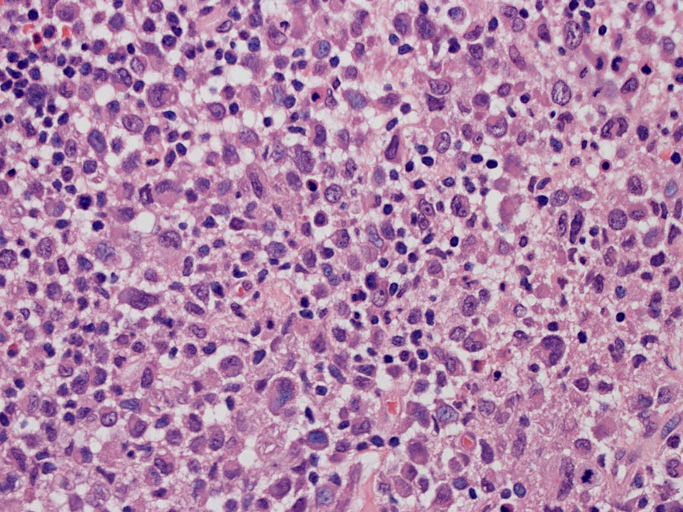

LCSの病理組織所見

Langerhans cell histiocytosisの高悪性度 variantで明らかな悪性像を示すLangerhans cellの腫瘍性増殖と定義される(WHO, 2008)

大型細胞の増殖よりなる腫瘍。縦溝,しわ,切れ込みのある核をもった大型細胞も出現する。クロマチンは顆粒状で核小体も明瞭である。核分裂は >50/10hpfと多い。eosinophilsは少ない。壊死が多発することがある。未分化ないし低分化な細胞像, 組織所見のため鑑別診断は多岐にわたり、的確な免疫染色を行う必要がある。